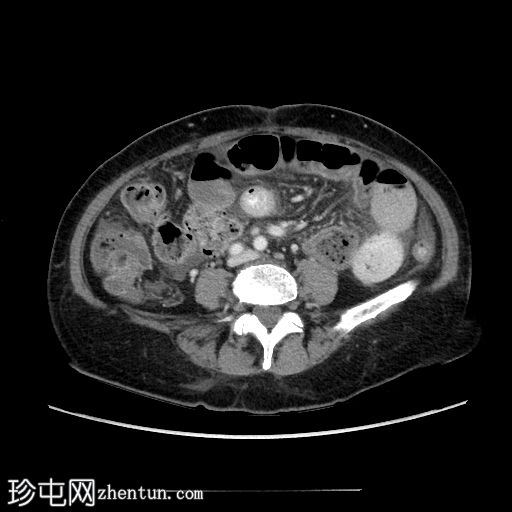

轴位增强扫描(门静脉期)

回肠末端长段狭窄,管腔狭窄,肠壁增厚/不规则,几乎延伸至回盲瓣。上游小肠节段扩张和粪便样改变,无重度梗阻。少量腹水。子宫切除术史。骶骨因放射治疗而相对脱钙。

病例讨论

典型的慢性放射性肠炎表现,导致狭窄和部分小肠梗阻。狭窄的

影像

表现多种多样,与放射野血管损伤引起的慢性缺血(闭塞性动脉内膜炎)有关。即使没有相应的临床病史,如果发现子宫缺失,骶骨和下腰椎呈脱矿质(更透亮)外观,也可以怀疑这种诊断。